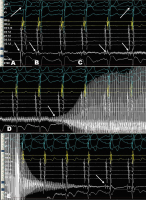

Abbildung 5: Intrakardiale Elektrogramme während der Kryo-Ablation. His-Katheter liegt im rechten Ventrikel, CS-Katheter in CS-Position, Kryo-Tip-Ablationskatheter (Abl) am atrialen Exit der parahisären akzessorischen Leitungsbahn. (A): Unter Ruhebedingungen zeigt sich im Sinusrhythmus ein Fusionspotenzial am Abl mit frühester ventrikulärer Erregung. Im Oberflächen-EKG zeigt sich eine deutliche Präexzitation. (B): Start des Kryo-Mappings mit Artefaktbildung auf der Ableitung des Abls (Pfeil). (C): Während des Kryo-Mappings Verlust der Präexzitation im Oberflächen-EKG mit Auftauchen des His-Signals am Abl (Pfeile). (D): Nun Start der Kryo-Ablation nach 40 Sekunden (Pfeil). (E): Nach Beendigung der vierminütigen Kryo-Ablation zeigt sich am Abl ein großes, klassisches His-Signal.